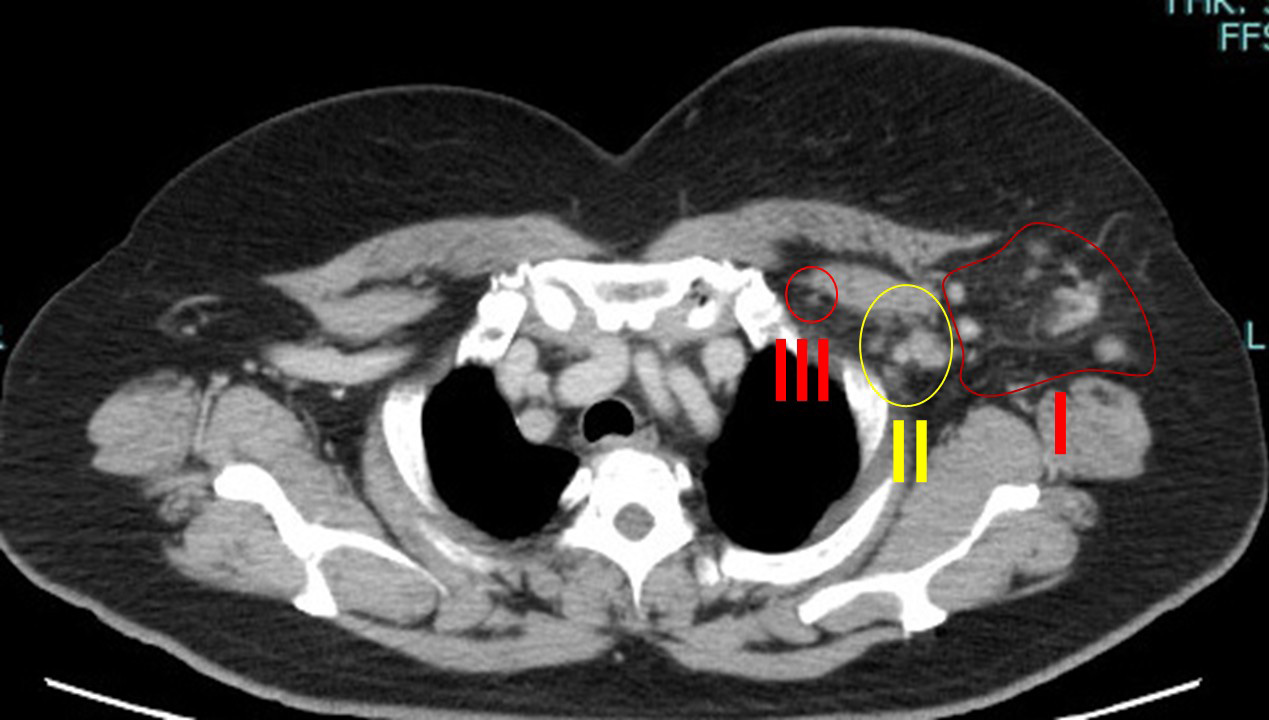

他院、初診時のCT

皮膚肥厚を伴う大きな腫瘍

リンパ節転移も腋窩(Ⅰ+Ⅱ)鎖骨下(Ⅲ)

両方に著明

前医で「手術不能乳癌、薬物療法しかできない」と、言われ当院を受診

注1)(我々は)フェスゴ+DTXx4クールでoperative(手術可能)になるとは考えにくいと考えていること

→実際に手術可能となったわけだけど…

それでも私は全摘+腋窩鎖骨下郭清しています。

この部分は(実は)彼らの「技術レベルの低さ」を露呈しているのではないか?と思っている。

そもそも「鎖骨下に転移がある」時点で、(自分たちの手に負えない)=手術できない(しても仕方がない)としか見ていないように思う。